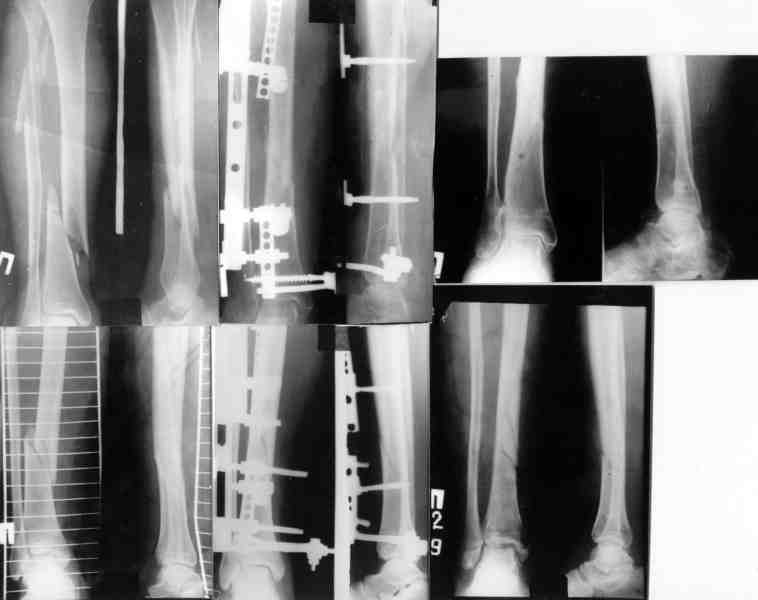

ММВ> выполнен закрытый блокируемый остеосинтез. Клинически результатом

ММВ> доволен. Рентгенологически - не вполне. нужно было погрузить стержень

В целом можно поздравить, очень неплохо. Рассверливали ли канал? Вверху вроде один винт, и в динамическом отверстии - лучше бы в статическое, а то стержень можт еще вылезти. А что за стерюень? Похоже на ChM. Из-за того, что выстоит, либо придется удалять рано или поздно. Либо через 2-3 мес. сделать ревизию - извлечь фиксатор, канал немного углубить и рассверлить, и тот же стержень ввести уже поглубже.

В дистальном отделе хватит и одного винта, лучше переднезаднего, чтобы поберечь лучевой нерв.

Канал не рассверливал. Стержень 7мм.ChM. В статическое отверстие не стал вводить винт, побоялся попасть в пустоту, а зря. Лучевой нерв видел,когда вводил дистальные винты. Антибиотики сменены, но складывается впечатление, что они не нужны.

> Канал не рассверливал. Стержень 7мм ChM. В статическое отверстие не

> стал вводить винт, побоялся попасть в пустоту, а зря.

Там есть выкол латеральной стенки, опасения понятны. В таком случае можно стержень повернуть на 90 градусов, чтобы проксимальные отверстия стали передне-задними. Тогда и дистальные винты через направитель можно вводить спереди назад (или сзади наперед).